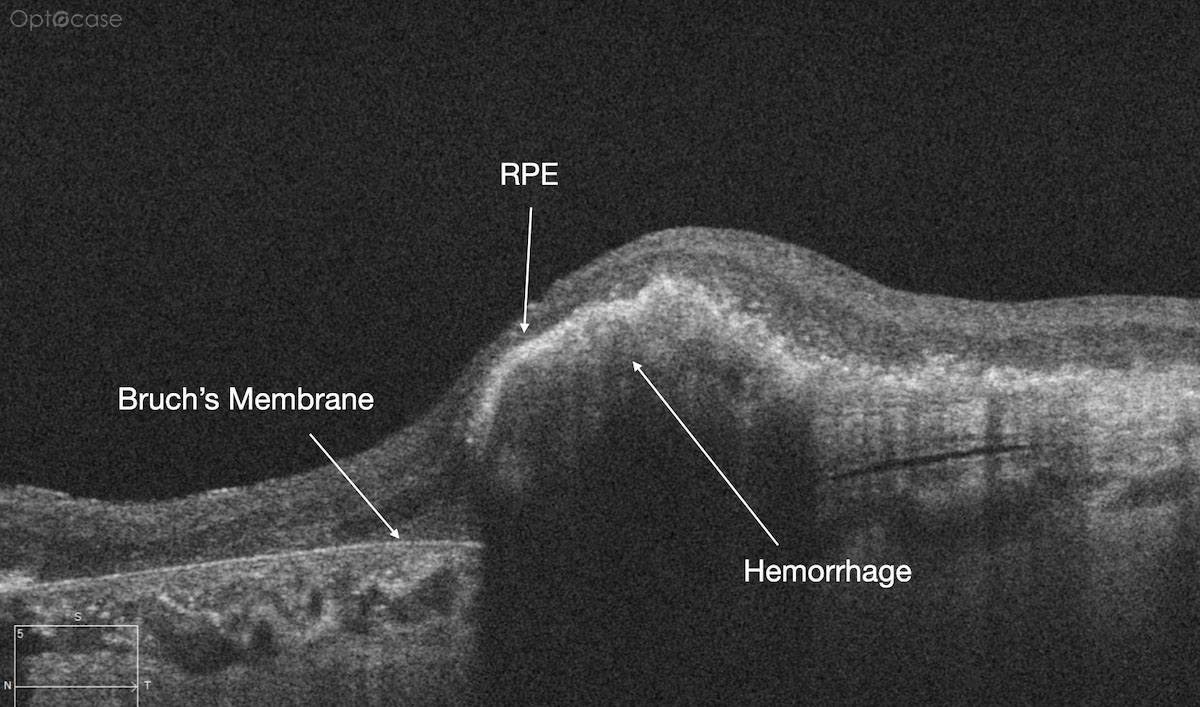

Here there is loss of the regular macular depression. There is a bright line present on the surface of the retina. In addition, there is separation of the retinal layers in the inner retina.

The patient was diagnosed with a schisis secondary to an epiretinal membrane. This complication is seen in over 50% of ERMs (video).

In any patient with intraretinal fluid consider the possibility of an epiretinal membrane causing a schisis.